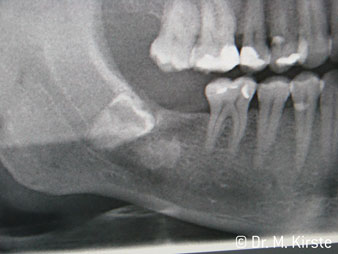

45° açılı angldruva geniş avantaj yelpazesi sebebiyle özellikle seçildi. Bu enstrümanın geliştirilme nedeni olan cerrah meslektaşlarım angldruvaların kısıtlı alanlardaki çalışma yeteneğini yakında takdir edeceklerdir. Özellikle gömük diş çekimlerinde (res. 2) yumuşak dokunun yanak bölgesine doğru yarılmasına gerek kalmaz(res. 3). Angldruvanın kafa dizaynı sayesinde retromolar bölgede hızlı ve güvenli çalışma sağlar.

Angldruva kafası içindeki profesyonel tasarımlı dişliler frezin sessiz çalışmasını garanti eder; kök separasyonu yapılırken atravmatik operasyona olanak verir. (res. 4-9).

Fig. 2

Fig. 4